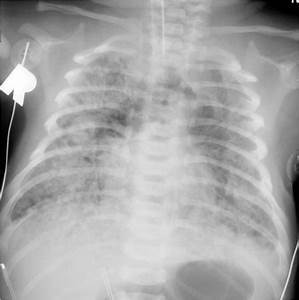

RN termo/pós-termo, que passou por SFA ou reanimação, banhado por liquido meconial, com quadro de desconforto respiratório GRAVE nas primeiras horas de vida (taquipneia, tiragem, retração, BAN, cianose, gemência), Rx com infiltrado GROSSEIRO e volume pulmonar aumentado

Diagnóstico, fisiopatologia, e tratamento?

Síndrome da aspiração meconial

Asfixia faz relaxar esfincter anal fetal, eliminando mecônio, feto aspira para vias aéreas inferiores, causando obstrução expiratória, pneumonite quimica, infecção secundária

Desconforto grave com infiltrado gorsseiro, podendo causar pneumotórax

Tratamento: suporte e surfactante